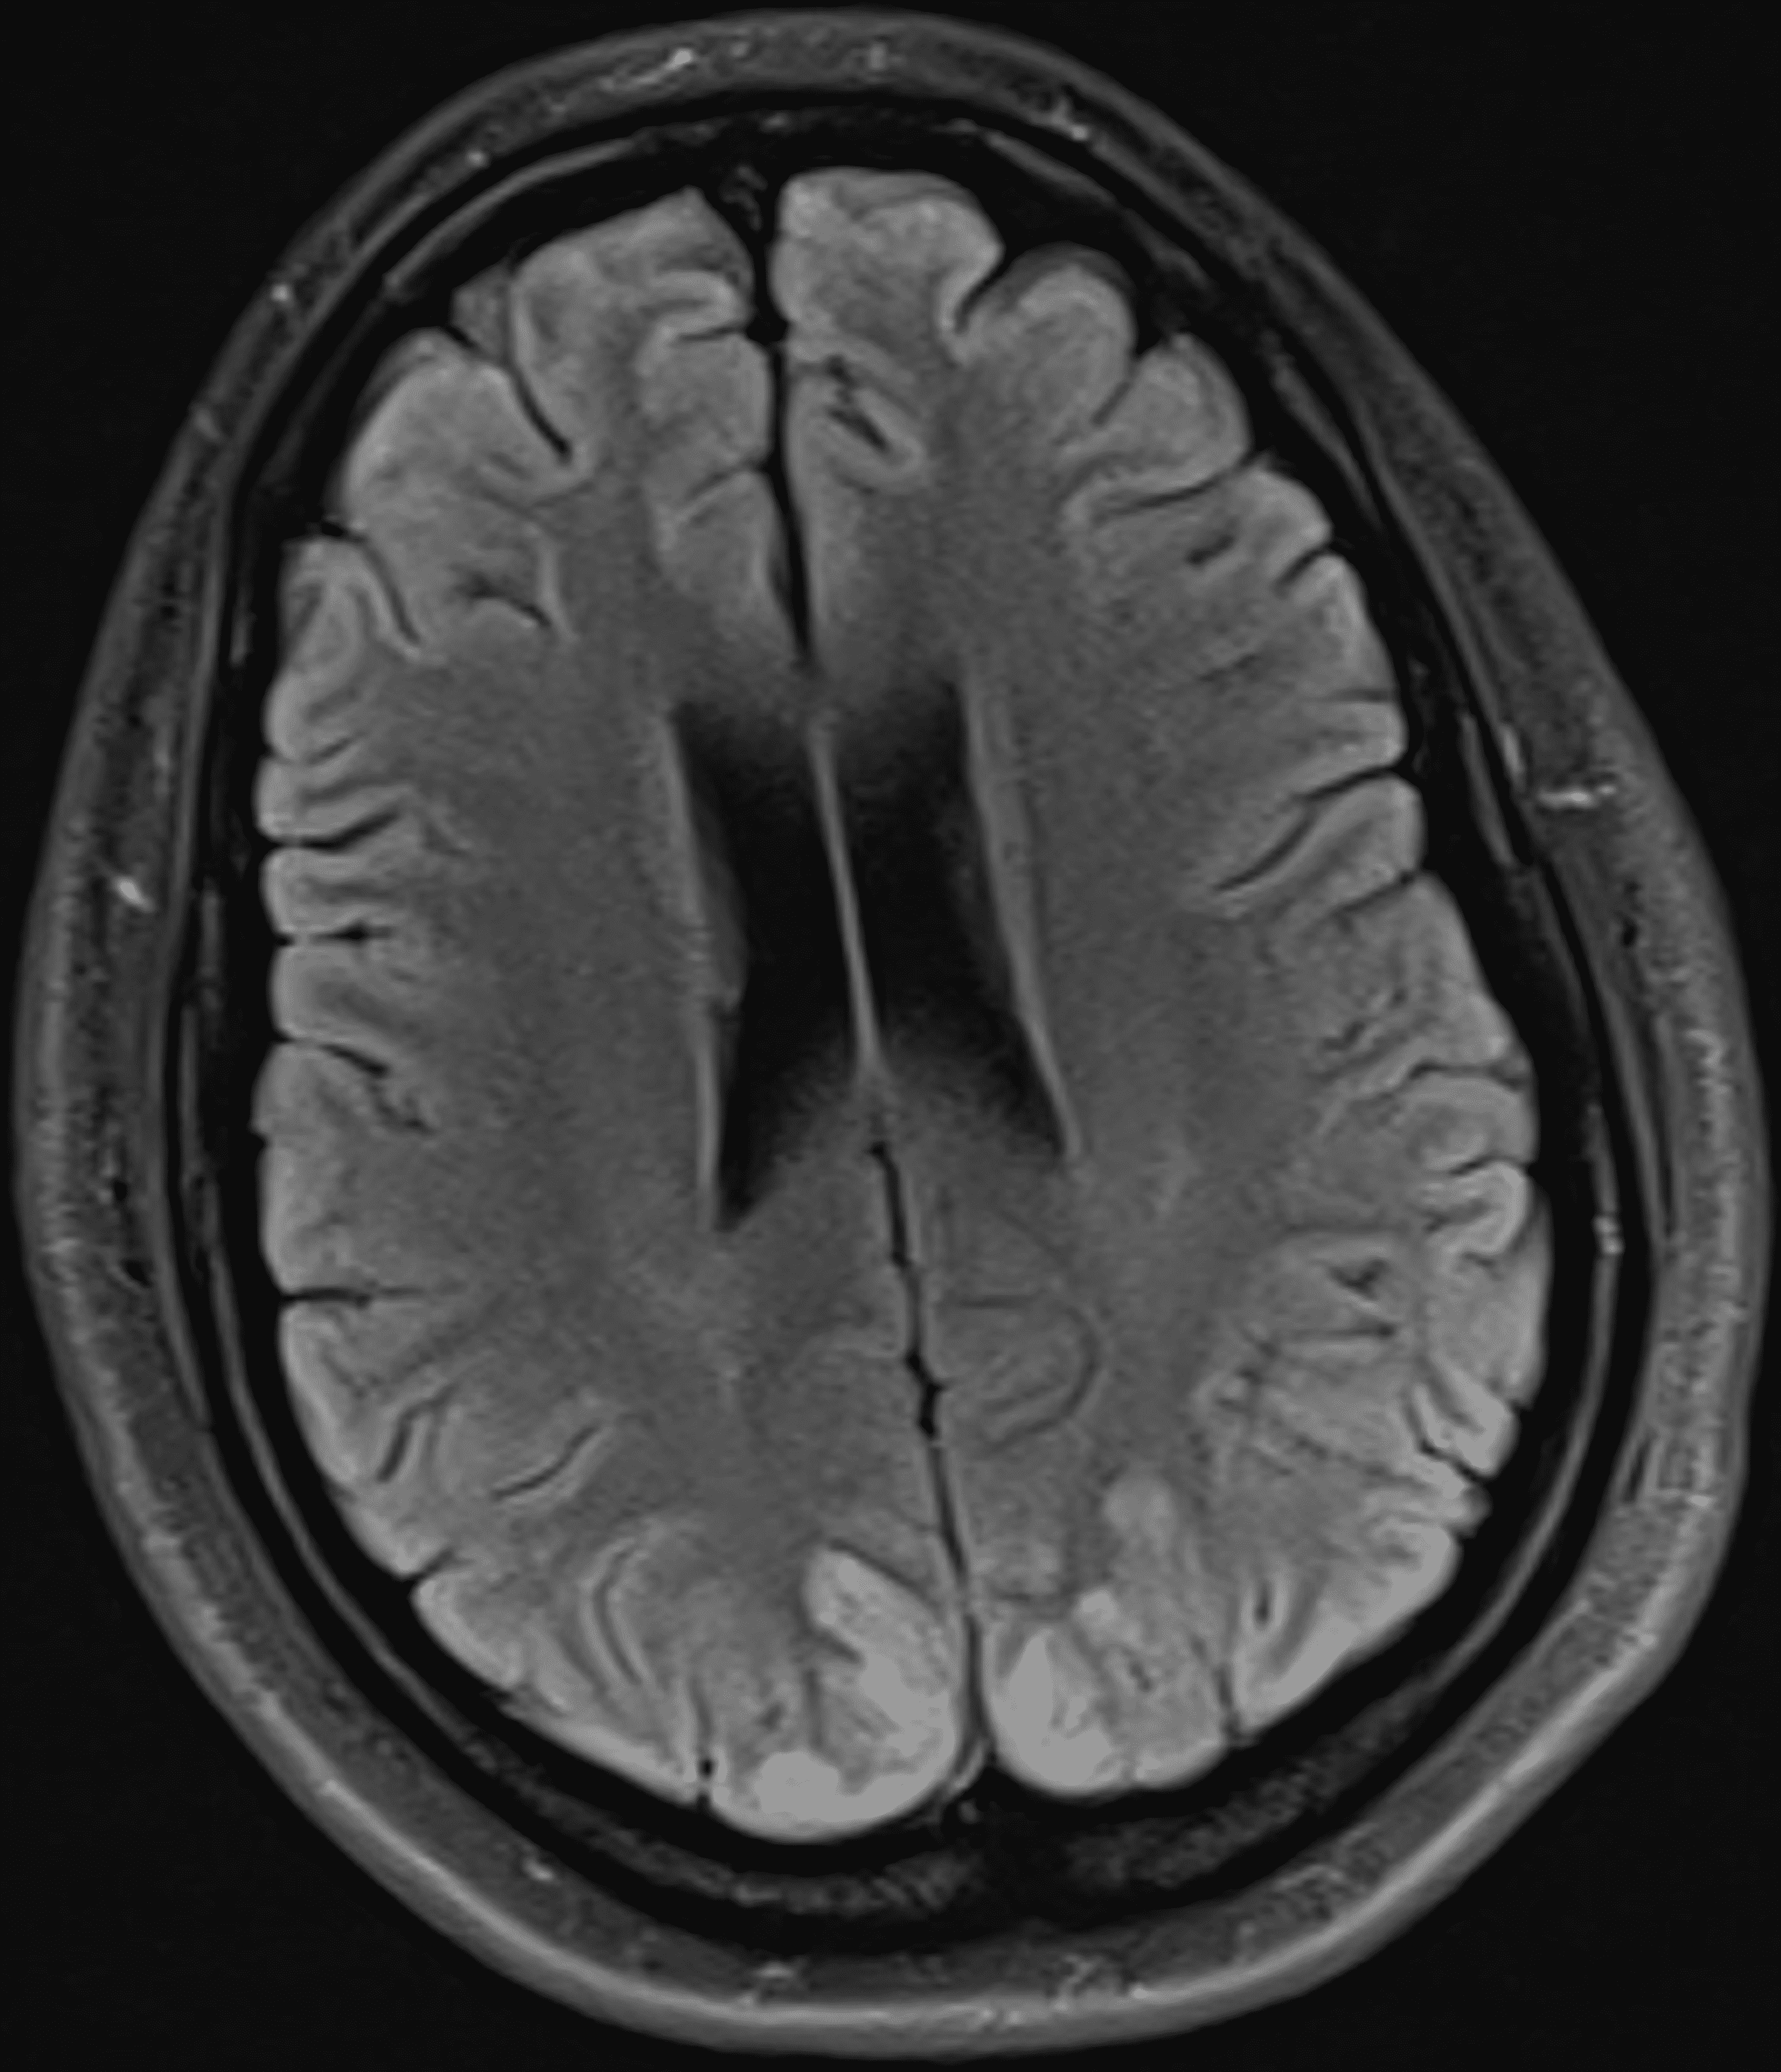

29yearold female patient with posterior reversible encephalopathy Eclampsia Encephalopathy Posterior reversible encephalopathy syndrome (pres) is an acute and transient neurologic condition with variable clinical manifestations including headaches, visual impairment. Posterior reversible encephalopathy syndrome (pres) 1,2 is an acute or subacute cerebral syndrome, the main manifestations of which are headache, encephalopathy,. Recognized in the setting of a number of complex conditions (preeclampsia/eclampsia, allogeneic bone marrow transplantation, organ transplantation, autoimmune disease. Eclampsia Encephalopathy.